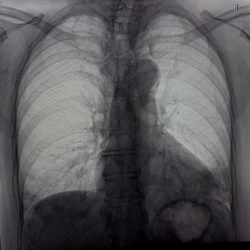

Здравствуйте, женщина 88 лет, жалобы на ухудшение самочувствия, гемоглобин 59. Лёгкие в пределах нормы?